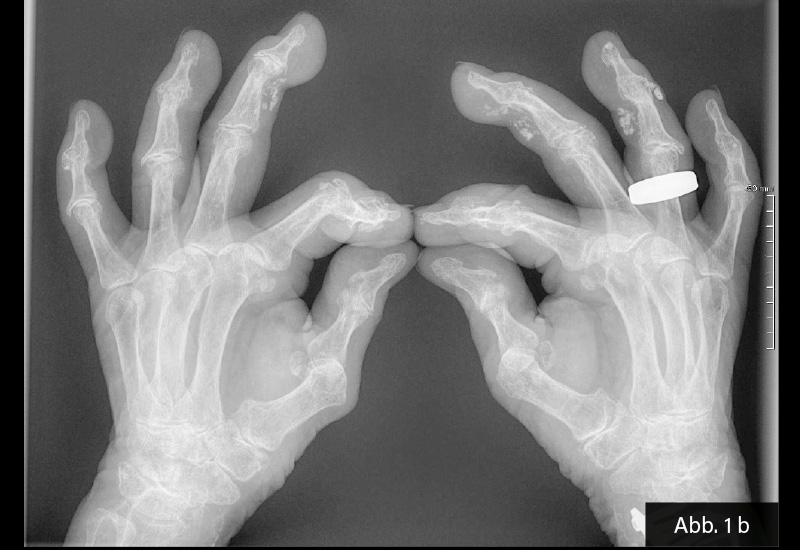

KLINISCHER BEFUND: 155 cm, 59 kg, RR 120/80, Puls 64/min. Gelenkstatus: Derbe Auftreibungen an einzelnen Fingermittel- und Fingerendgelenken im Sinne einer Fingerpolyarthrose (Heberden- und Bouchard-Typ). Haut: Calcinosis cutis, unter anderem an D IV der rechten und D III der linken Hand.

BILDGEBENDE DIAGNOSTIK: Röntgen s. u.

DIAGNOSE: Calcinosis cutis bei CREST-Syndrom

Die Bildgebung bei Calcinosis cutis dient der Erfassung und Charakterisierung von Kalkablagerungen in Haut und Subkutis. Für den Nachweis und die Ausbreitung der Verkalkungen werden häufig konventionelle Röntgenaufnahmen eingesetzt, da diese die Kalkdepots meist deutlich sichtbar machen. Die Sonografie kann kleinere Verkalkungen, ihre Morphologie sowie die Tiefe und das Ausmaß der Läsionen darstellen. Bei unklaren Befunden oder ausgedehnter Beteiligung eignet sich die Computertomografie (CT) zur exakten Lokalisierung und Quantifizierung von Kalzinosen. Die Magnetresonanztomografie (MRT) ist zum Nachweis von Kalk weniger sensitiv, kann aber hilfreich zur Beurteilung des umgebenden Weichteilstatus sein. Radiologische Methoden sind entscheidend zur Differenzierung gegenüber anderen Ablagerungsdermatosen (z. B. Ossifikation, Amyloidose).